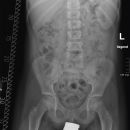

Beckenübersicht a.-p.

Fraktur, Luxation und degenerative Veränderungen (Coxarthrose)

Das Becken stellt sich vollständig, symmetrisch und gleichmäßig gut belichtet dar, einschließlich beider Hüftgelenke und der Trochanteren. Trochanter major darf den Schenkelhals nicht überlagern und der Trochanter minor ist gerade erkennbar.